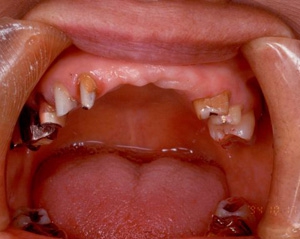

両側5歯症例 主訴-義歯のバネが壊れて手前の歯が痛んできた。 術前(旧義歯装着、鏡像)

術前(下顎粘膜面、鏡像)

術前口腔内(正面観)